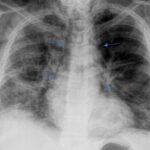

Dentro de los métodos diagnósticos, el neumomediastino se puede diagnosticar mediante radiografías o tomografía computada, donde se va a visualizar la presencia de aire (radiolucidez o hipodensidad lineales) rodeando las estructuras mediastinales. Un signo de muy alta especificidad es el llamado “signo del anillo alrededor de la arteria”, donde se visualiza una imagen radiolúcida o hipodensa en forma de anillo rodeando la arteria pulmonar, principalmente del lado derecho. Este signo ayuda a diferenciar esta entidad del neumopericardio, que puede verse similar en imágenes.

Among the diagnostic methods, pneumomediastinum can be diagnosed using X-rays or computed tomography scans, where the presence of air (linear radiolucency or hypodensity) surrounding the mediastinal structures will be visualized. A highly specific sign is the so-called “ring sign around the artery”, where a radiolucent or hypodense ring-shaped image is visualized surrounding the pulmonary artery, primarily on the right side. This sign helps differentiate this condition from pneumopericardium, which can appear similar on imaging.

De los casos mencionados anteriormente, en el 76,3% (29) el neumomediastino se encontraba asociado a otro signo (10 pacientes presentaban dos signos acompañantes). Dentro de estos se encuentra el enfisema subcutáneo (65%), neumotórax (18%), neumoperitoneo (8%), neumopericardio (2,6%) y enfisema de músculos paravertebrales (2,6%).